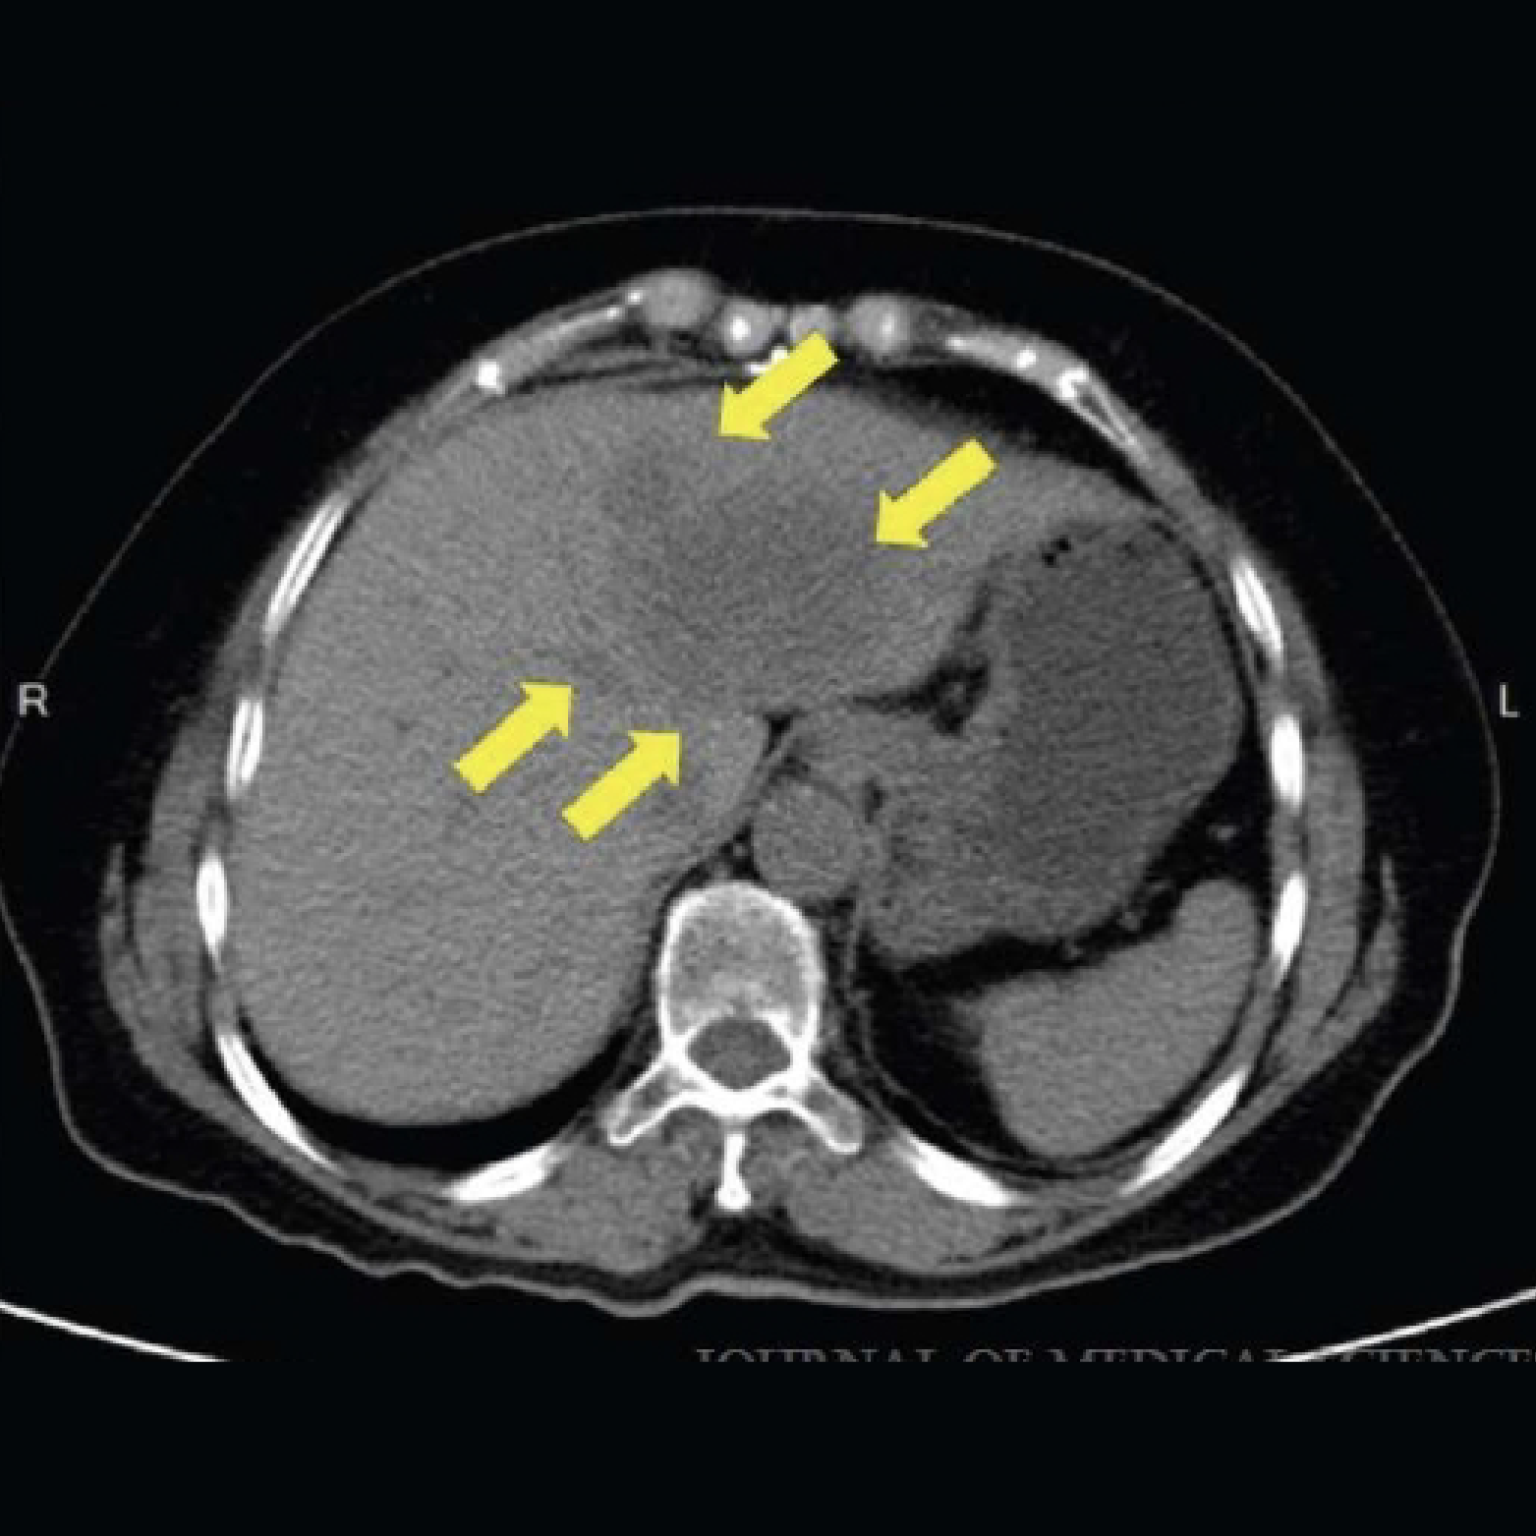

腹部電腦斷層掃描在Osimertinib治療期間顯示顯影不良的肝臟腫塊,可能為肝轉移。

一ㄘ名轉移性肝腫瘤的非小細胞肺癌 (NSCLC) 患者,

在接受為期 24 週的自體免疫殺手細胞 (IKC®) 治療後,

成功治療後未再發現肝轉移腫瘤。